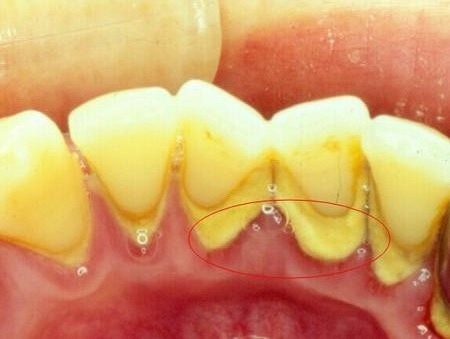

2.牙结石是由菌斑长时间堆积后钙化形成,质地很硬,像石头一样。所以牙结石是刷不掉的。

若菌斑附着在牙体,长时间没去除,就形成了牙结石。牙结石自己脱落小妙招。

3.细菌喜欢在温暖,并有足够食物的地方寄居。人的口腔给多种细菌提供了理想的生存空间,它们的其中一些还在牙齿上形成叫做牙斑的糊状膜。牙斑驻留驻留时间太长,就会慢慢矿化,形成结石或酒石。牙结石是类似石头的物质;由于提供给细菌更多积聚表面,因此这种结石会进一步导致牙科疾病。

洗牙洗掉的就是河马牙医科普了那么久的牙结石啦!(牙结石就是、棕色甚至黑色的、存在于牙齿的颈部与表面(比如下前牙的舌侧表面)等地方、并且会时不时散发出恶臭还牙龈的坏东西。)

日常的刷牙只能清除牙齿和舌苔表面的食物残渣菌斑;而牙线也只能清除齿缝深处的刷牙无法刷到的菌斑。所以,就算你刷牙刷得特别溜、牙线用的超勤快,总也阻止不了有些顽固牙菌斑躲在隐蔽的角落暗暗壮大,努力钙化变成牙结石,对口腔健康形成威胁。更不要说大部分的人其实根本刷不来的牙,也几乎不用牙线。